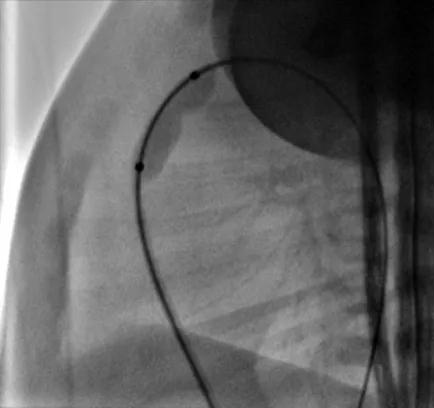

东院区新生儿科医护团队给予患儿精心的护理和细致的术前准备。患儿出生第6天,在新生儿科和麻醉科的密切配合下,王玉林教授在东院区介入中心为患儿实施PBPV。麻醉科医生成功为患儿实施了全身麻醉,术中王玉林教授先后选用4.5×15mm冠脉球囊和8×20mm球囊导管分别扩张肺动脉瓣,扩张后导管测量右室压力由71mmHg降至21mmHg,血氧饱和度由术前的80%即刻升至90%以上,手术效果良好,顺利完成后患儿安全返回病房,无任何并发症。

术中球囊扩张图片

术后患儿返回东院新生儿科继续密切监测生命体征,复查超声心动图显示跨肺动脉瓣压差29mmHg,三尖瓣中度反流,动脉导管闭合;患儿血氧饱和度逐渐维持在95%~100%,自行纳奶等一般情况良好,于8月13日顺利出院。